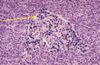

Identify the following features of the normal pancreas

Top 2 are B cells - that secrete insulin. about 2/3 of the islet is made of these

Bottom shows a capillary - where insulin, glucagon etc are drained away

What is shown here?

Lymphocytes in the islets (insulitis)